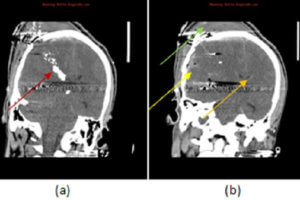

Penetrating Head Trauma

Trauma accounts for approximately 1 in 3 ER visits nationwide and is a major public health problem. It is the leading cause of death amongst youth and young adults and a major... Read more »